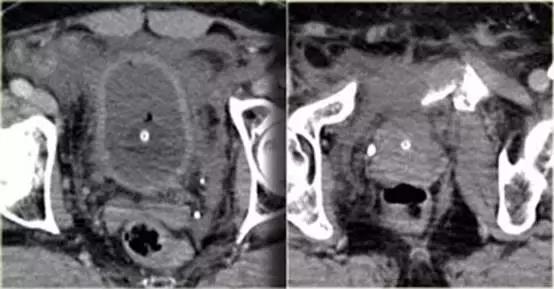

同一病人的CT常规增强检查

结果

有一个指向膀胱的骨盆骨折碎片。

膀胱直肠隐窝积液。

膀胱造影前后CT对比图像

膀胱中导尿管有对比剂, 膀胱直肠隐窝中也有渗出的对比剂。